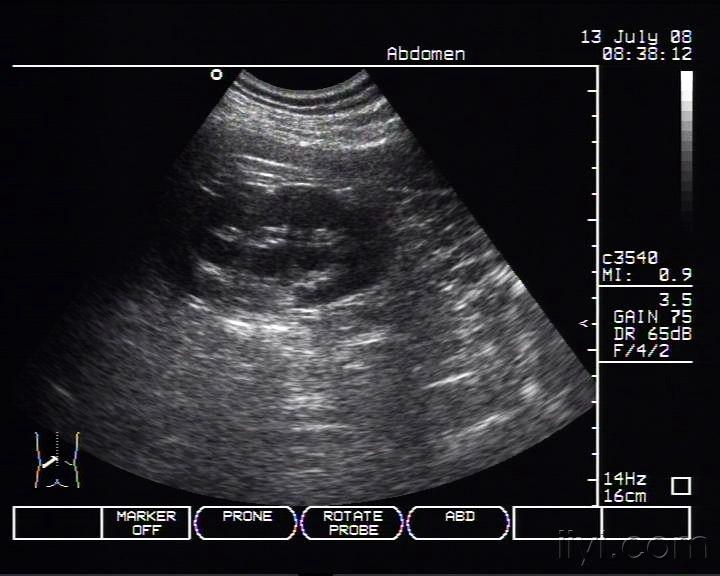

病例分析:双肾积水,集合系统分离【多图】

图片尺寸2448x3264